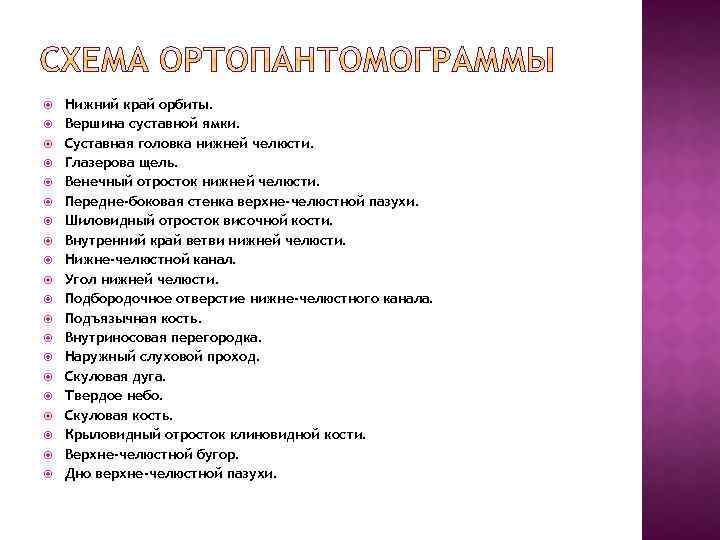

Нижний край орбиты. Вершина суставной ямки. Суставная головка нижней челюсти. Глазерова щель. Венечный отросток нижней челюсти. Передне-боковая стенка верхне-челюстной пазухи. Шиловидный отросток височной кости. Внутренний край ветви нижней челюсти. Нижне-челюстной канал. Угол нижней челюсти. Подбородочное отверстие нижне-челюстного канала. Подъязычная кость. Внутриносовая перегородка. Наружный слуховой проход. Скуловая дуга. Твердое небо. Скуловая кость. Крыловидный отросток клиновидной кости. Верхне-челюстной бугор. Дно верхне-челюстной пазухи.